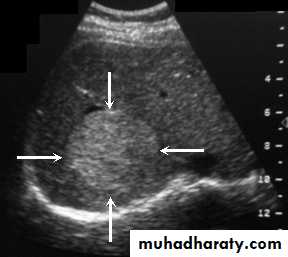

Focal masses ultrasound

Hemangioma